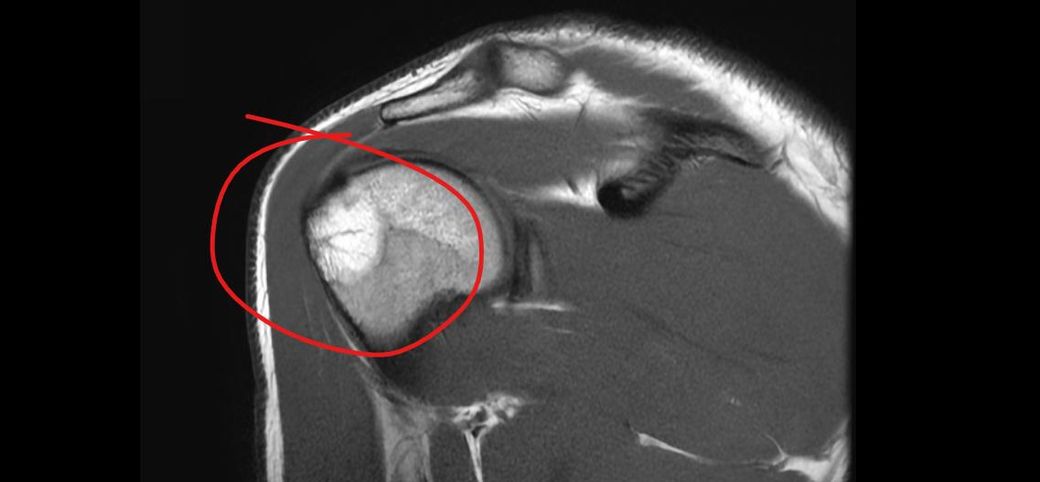

어깨 골수부종인가요 ? 뼈멍인가요 미세골절인가요 사고나고 뼈에 심하게 멍들었다고 했긴했습니다 전 잘모르겠어서 질문 해봅니다

• 3번 째 사진

사진만으로 단정은 어렵지만, 표시된 소견은 보통 “골수부종(=뼈멍)”에 가장 가깝습니다.

골수부종은 “강한 충격 후 뼈 안에 물이 찬 상태“로, 미세골절과 영상상 겹쳐 보일 수 있습니다.

“미세골절”은 골수부종보다 통증이 오래.강하고 체중부하/사용 시 악화되는 경우가 많습니다.